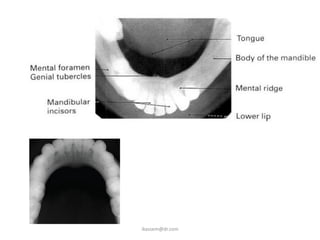

This projection shows a plan view of the tooth bearing

portion of the mandible and the floor of the mouth. A

minor variation of the technique is also used to show

unilateral lesions.

Note: The lower 90° occlusal is mounted as if the

examiner were looking into the patient's mouth.

The radiograph is therefore mounted with the

embossed dot pointing away from the examiner.